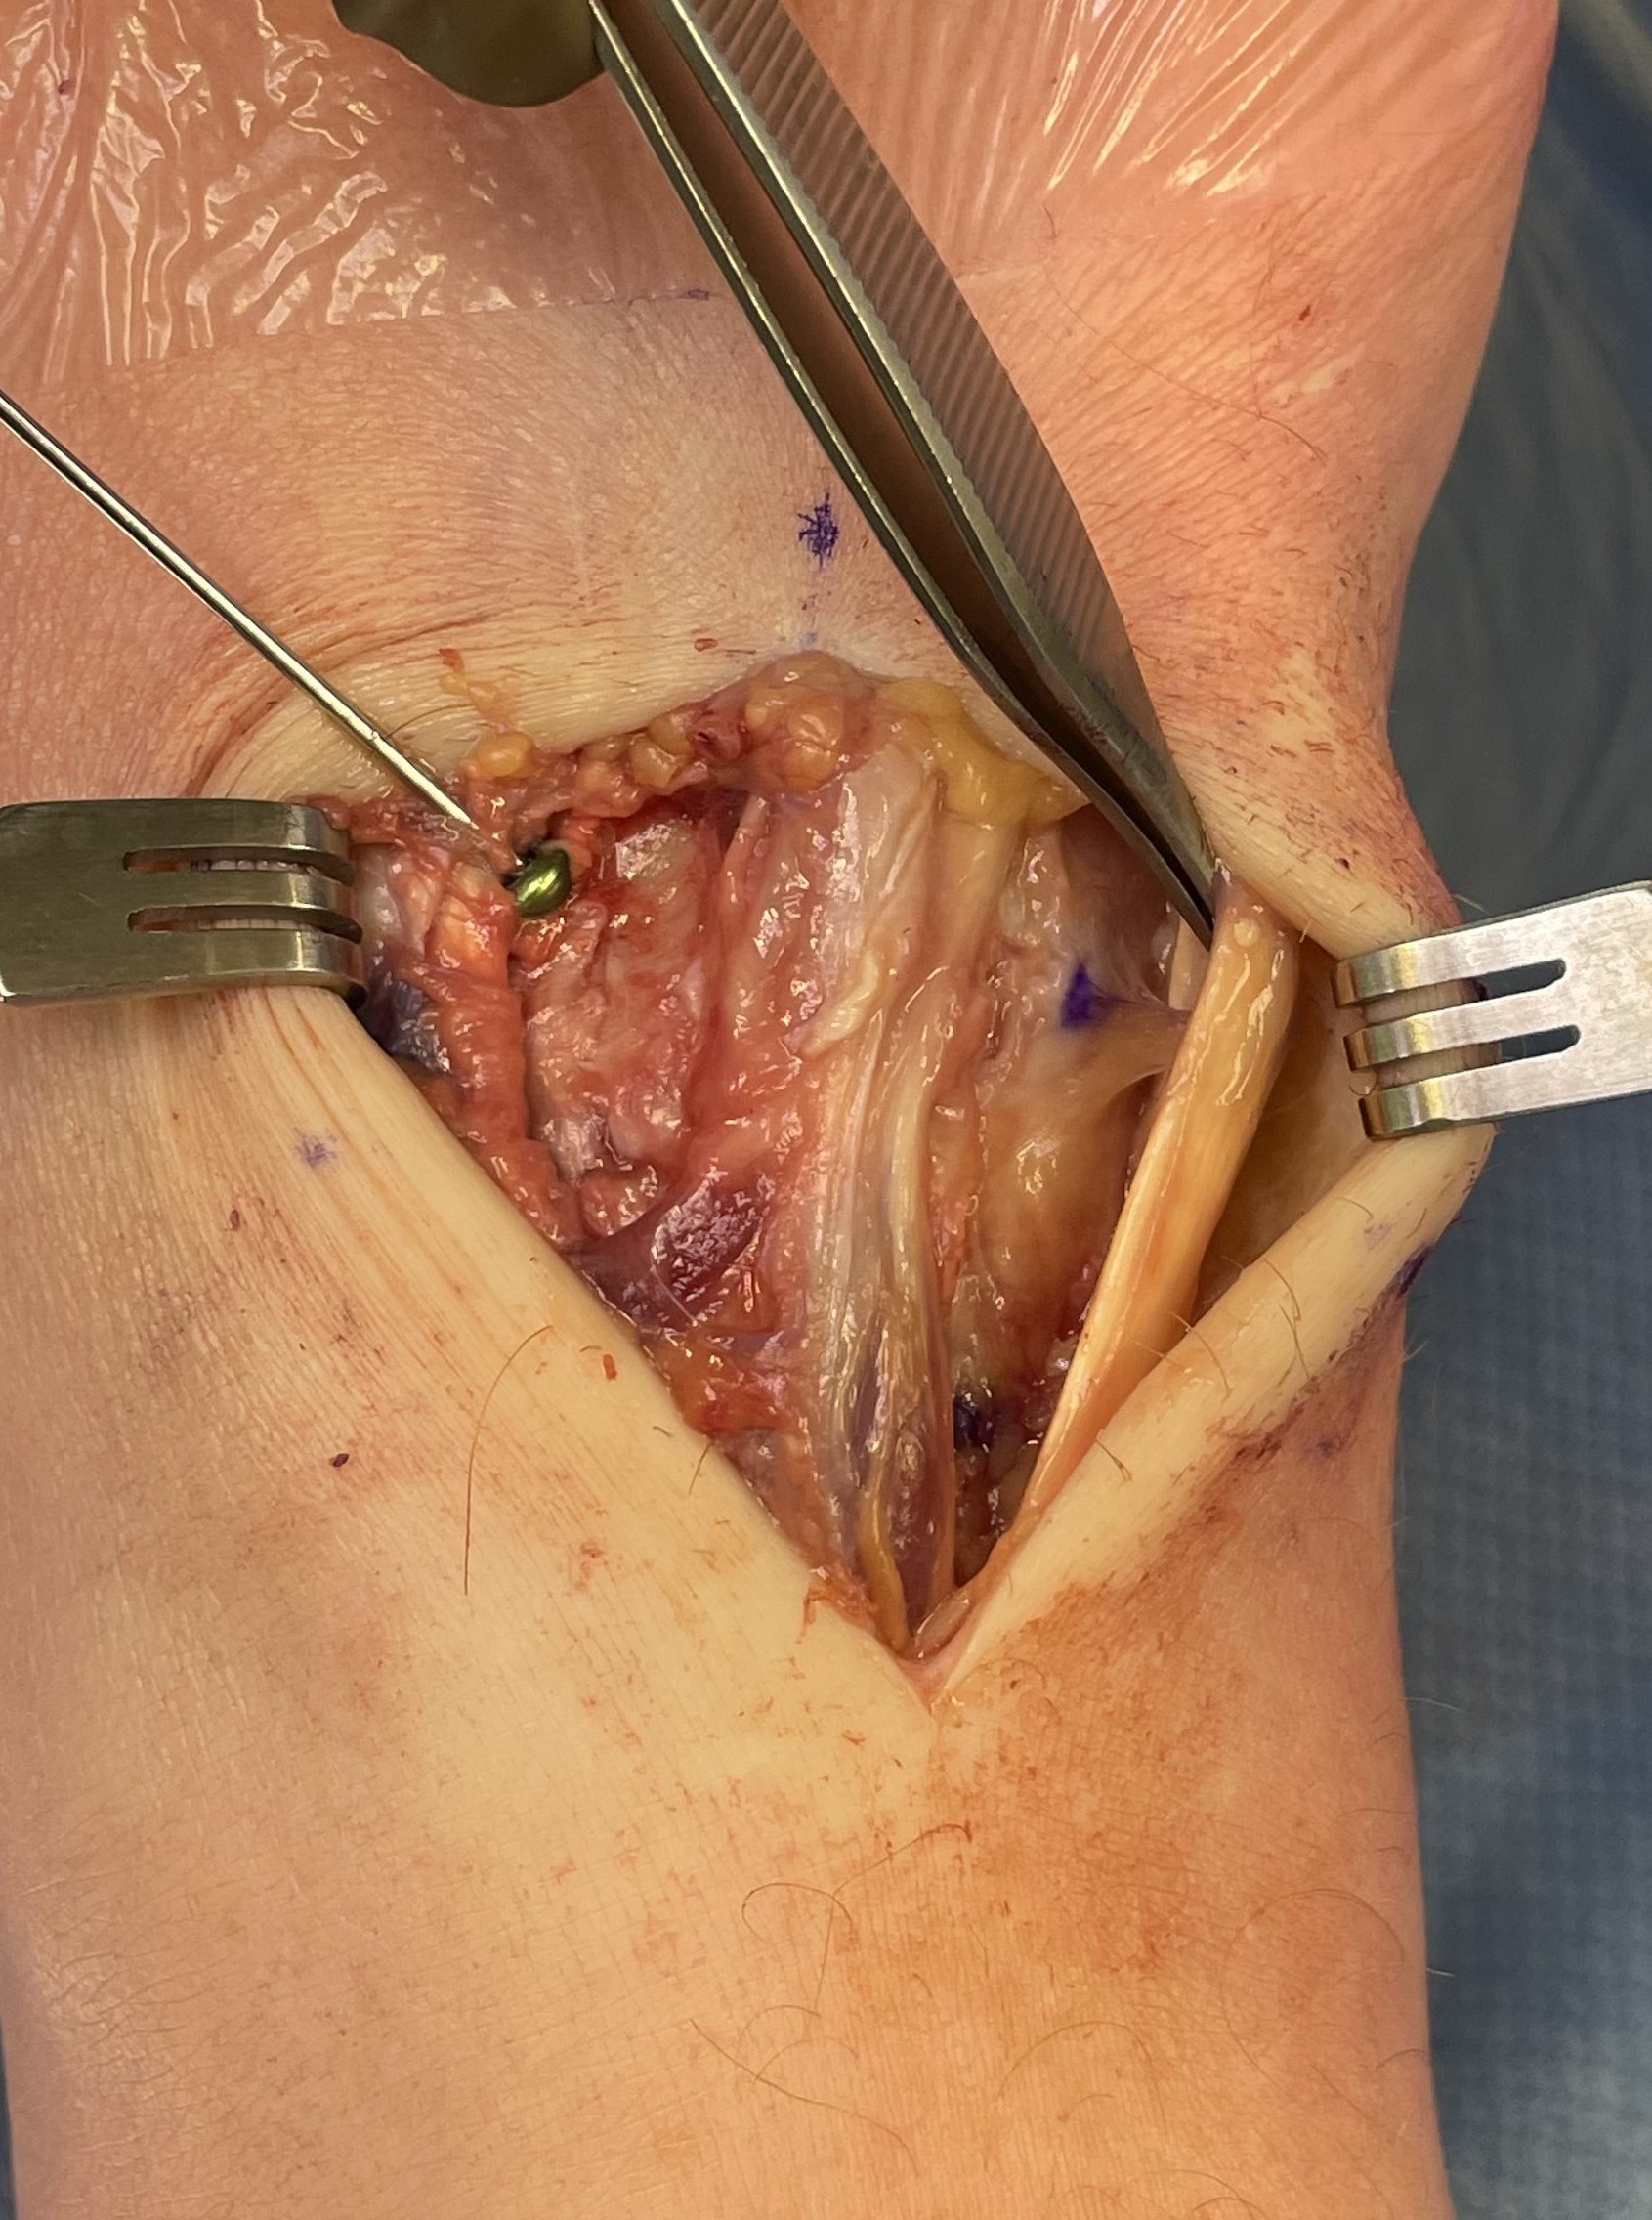

Approach and reduction

Dorsal incision between 1st and 2nd metatarsal

- protect branches of superficial peroneal nerve

- release EHL tendon and retract laterally for 1st TMT / medially for 2nd TMT

- retract EDB more proximally either way to approach 1st TMT / 2nd TMT

- pass artery clip under dorsalis pedis / deep peroneal nerve and mobilize

Reduction

- medial incision over medial cuneiform

- clamp medial cuneiform to base 2nd metatarsal